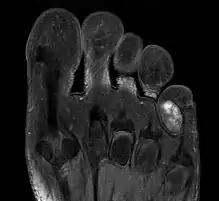

1. IRM d'un chondrome extérieur sur un petit doigt de pied.